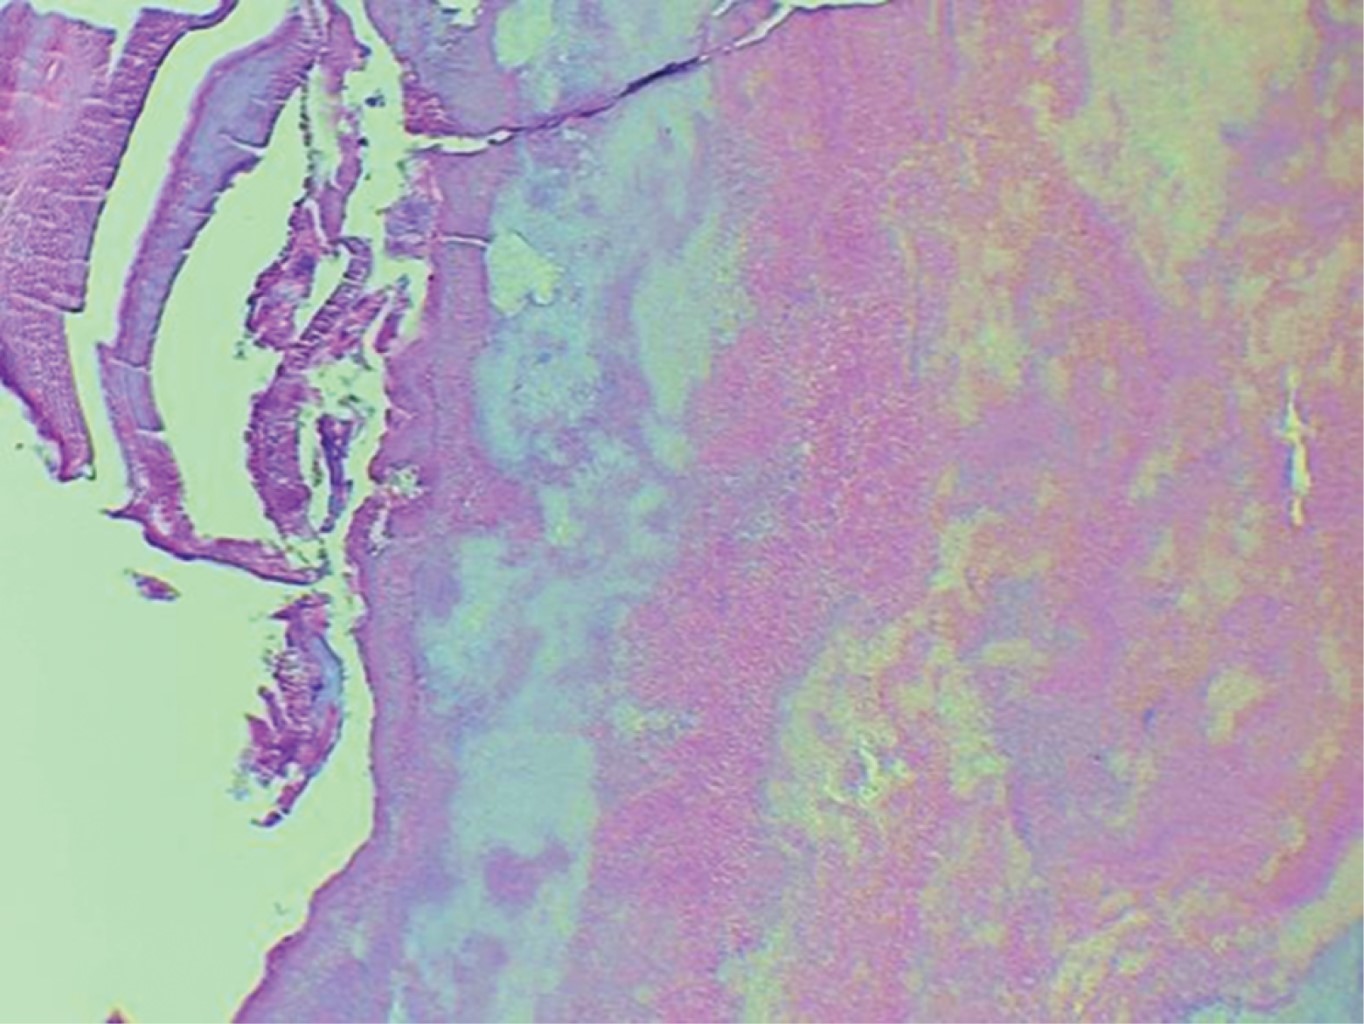

Introduction: Küttner's tumor or chronic sclerosing sialadenitis (CSS) is a rare disease of the major salivary glands. It is characterized by an increase in volume, usually unilateral, although its presence has also been reported in minor salivary glands with or without a relationship with IgG4 disease, producing a fibroinflammatory infiltration in the interlobular septa, but its architecture is preserved and in some cases the presence of stones and positive IgG4 cells. Material and methods: a 44-year-old female patient with tomographic findings of calcification of the left submandibular glands, for which surgical excision of the gland was performed, obtaining a histopathological diagnosis of Küttner's tumor. Results: bimonthly follow-up of the patient continues, currently without the presence of alterations in relation to IgG4 disease. Conclusions: Küttner's tumor or chronic sclerosing sialadenitis (CSS) can sometimes be the initial or only finding of IgG4 disease. The timely diagnosis or the importance of ruling out IgG4 disease is due to all the autoimmune diseases related to it or its possible complications.

Figure 1